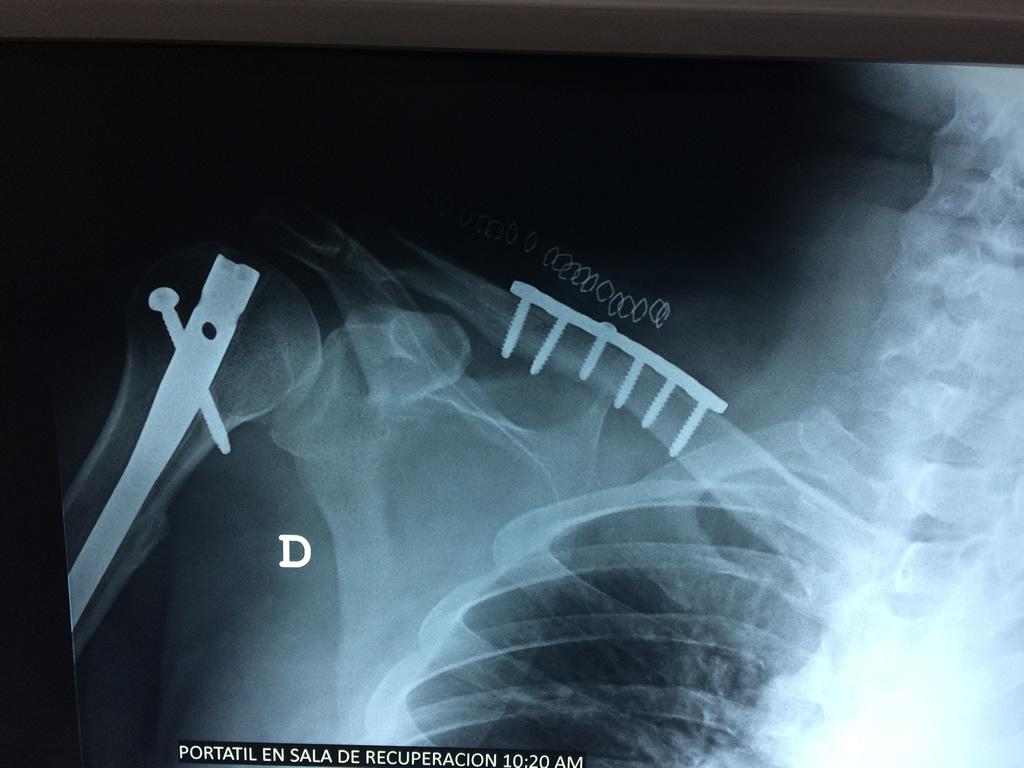

Cirugias en El Salvador - Clavícula